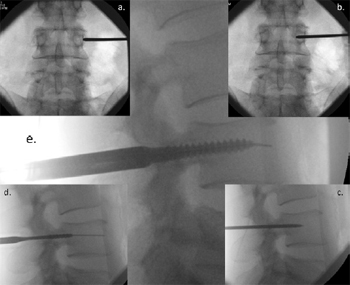

Fig. 2. Image Intensifier radiographs of the percutaneous technique for pedicle screw

insertion showing: (a) anterior/posterior (AP) view of the Jamshidi needle docked

onto the lateral aspect of the pedicle – the ''3 o'clock position''; (b) AP view of

advancement of the needle 20 mmto 25 mminto the vertebral body; (c) lateral view,

checking the position of the Jamshidi needle in lateral view; (d) lateral view, the Kwire

and tapping of the pedicle; and (e) lateral view, insertion of the pedicle screw.

- Place the II in the anterior/posterior (AP) position. The spinous

process should be midline between the pedicles to

ensure a direct AP projection (Fig. 2a).

- Mark the position of the lateral aspect of the pedicle on the

skin. Depending upon the depth of the tissue between skin

and pedicle, the skin incision should be made laterally

(Fig. 3) so that the Jamshidi needle can be angled appropriately

when inserting it into the pedicle.

- Place the Jamshidi needle through the skin incision and

''dock'' onto the lateral aspect of the pedicle (Fig. 2a). This

is called the ''3 o-clock'' position.

- Advance the Jamshidi needle 20 mm to 25 mm into the pedicle,

making sure the needle remains lateral to the medial

pedicle wall (Figs. 2b and 3).

- Position the II in the lateral plane. The Jamshidi needle

should now be in the vertebral body, and therefore ''safe''

with no risk of medial pedicle breach (Fig. 2c).

- Place a K-wire down the Jamshidi needle and place a pedicle

tap down the trajectory of the K-wire (Fig. 2d).

- Place the final pedicle screw with the screw placed down the

K-wire (Fig. 2e), making sure not to advance the K-wire

beyond the anterior aspect of the vertebral body.